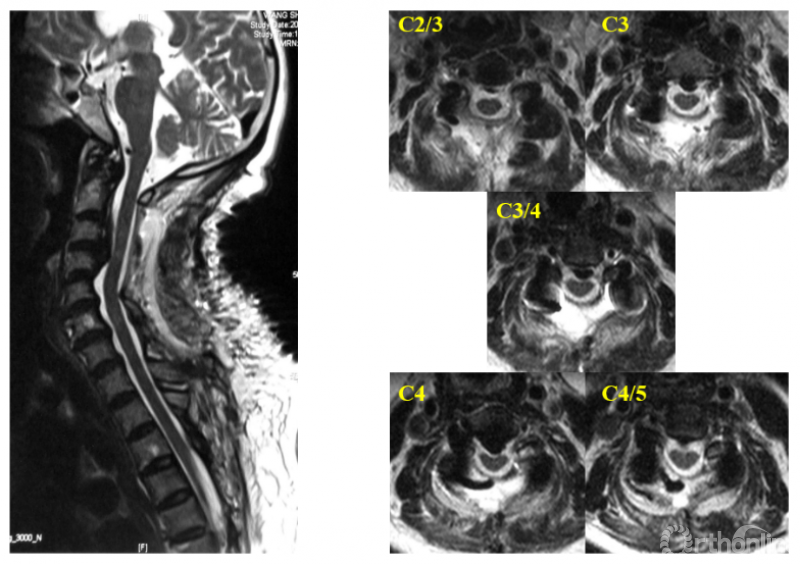

在本研究中,我们增加了不同减压范围的组别。对129例接受了颈后路减压手术且减压充分的患者的资料进行回顾研究,并且根据减压范围分为:C4-7组(n=11),C3-6组(n=61),C3-7组(n=32),C2-7组(n=25)。以后路术后椎髓间距(Vertebral body-Cord Distance, VCD)作为代表减压限度的参数:后路减压术后椎体后缘连线上各点至脊髓前缘的距离(图1)。

图1 椎髓间距(VCD)的测量

在充分避让了前方致压物的情况下,VCD代表了脊髓避让前方致压物的能力(与本系列研究第二节中的脊髓前间隙的测量方法相同,考虑到“间距”比“间隙”更能准确表达该参数的本质,并不是脊髓前方的腔隙,而是脊髓至椎体后缘的空间距离,该距离可被致压物部分充填但不影响其数值,可以与致压物进行数值上的比较,故作此改变)。通过测量并比较各组在C2-7每个节段上VCD数值,了解减压范围的对减压限度影响。

测量结果如图2所示。我们以测量的数据作图,纵轴显示各个颈椎节段,横轴代表VCD数值,得到的图片效果类似于在阅读颈椎核磁的矢状位图像,只不过人为将颈椎拉直了(图3)。

图2

图3

曲线左侧被颜色填充的部分,代表了各组在每个颈椎节段获得的VCD,致压物如果位于曲线左侧的区域内,就不会残留压迫。从这个动图可以看出,减压范围的变化会影响特定节段的减压限度。那么减压范围对减压限度的影响规律是什么呢?

我们还需要对每个节段的减压特征进行定义,根据目标节段在减压范围中所处的位置,可以分为边缘外减压、边缘内减压和中心性减压(图4),并且用关系符号标明数据表内各组数据的大小关系,最后将各节段的减压特征代入数据表中(图5)。

图4

图5

结果发现内在规律是:改变颈后路纵向减压范围会改变某些节段的减压特征,进而影响在该节段的减压限度。在不同的减压范围下,同一节段横向比较,减压限度的关系是:边缘外减压<边缘内减压<中心性减压,其减压限度的差异具有显著性;处于同一减压级别的节段之间减压限度没有差异;中心性减压已达该节段最大限度减压,不会随着减压范围的增加而增大。